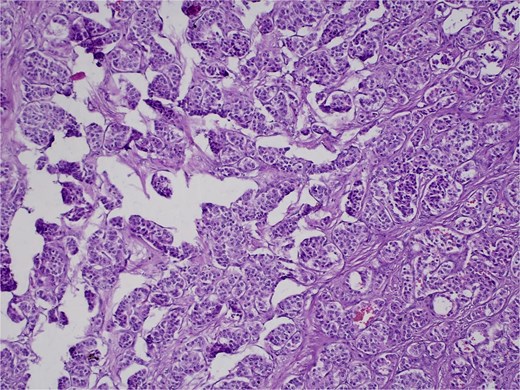

On 27 January 2025, the patient underwent a Whipple procedure (pancreaticoduodenectomy). The surgery included cephalic pancreatectomy with reconstruction through hepaticojejunostomy and gastrojejunostomy in a Roux-en-Y configuration. Gross pathology revealed a firm, white-yellow, indurated mass in the pancreatic head measuring 3.7 × 3.5 × 3 cm with irregular borders and central hardness (Fig. 4). Histopathological analysis confirmed a Grade 1 neuroendocrine tumor (insulinoma), with a Ki-67 index of 2%. The tumor showed direct extension to adjacent pancreatic tissue, the duodenal muscularis propria, the adventitia, and the muscularis of the common bile duct. Five peripancreatic lymph nodes were dissected, three of which were positive for metastases (Figs 5–9).

Hematoxylin and eosin (H&E) stain, 400× magnification. Tumor cells arranged in nested and trabecular patterns with round, hyperchromatic nuclei, and finely granular chromatin.